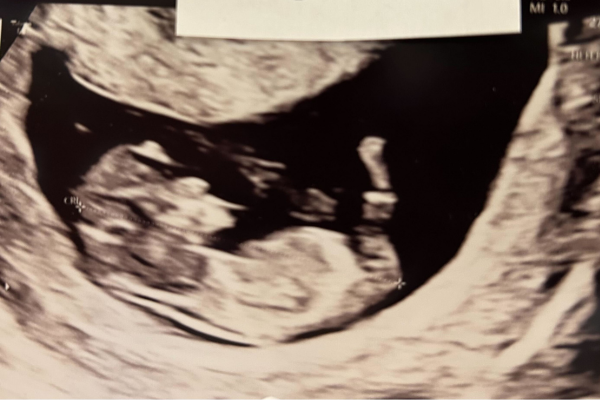

Gravid uge 11

Uge 11+0 – 11+6

Barnet vejer nu omkring 8 gram og måler cirka 44-60 mm fra toppen af hovedet og ned til numsen. Fra uge 11+4 er det muligt at lave nakkefoldsscanningen. Hjertet slår med 140-150 slag/min., præcis som det skal. Den takt er nødvendig for at pumpe energi ud til den lille krop, hvis den skal vokse og udvikles. Lige nu er hovedet lige så stort som resten af kroppen. Leveren er også stor, så den fylder næsten hele bughulen. Testikler eller æggestokke er på plads, og nu kan man også ane de ydre kønsorganer. Det er stadig svært at se om det bliver en dreng eller pige. Barnet kan åbne sin mund, og tungen er allerede færdigudviklet.